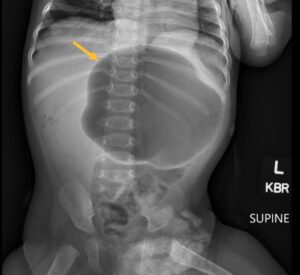

Incarcerated Gastric Volvulus and Splenic Herniation. Abdominal Radiograph. Annotated. JETem 2025